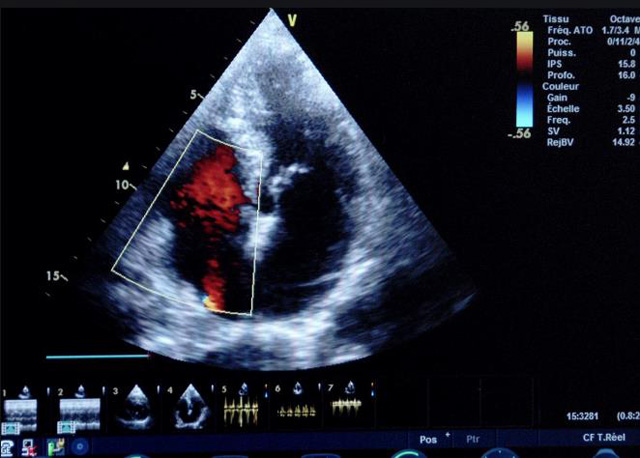

二、彩色室壁運動分析

(一)基本原理彩色室璧運動分析,從整體散射數(shù)據(jù)中識別心內(nèi)膜邊界,并與前一幀彩色不同,心臟收縮或舒張期開始到結(jié)束時心內(nèi)膜的全部過程。每一次順序顯示結(jié)束后,原來的彩色自動消失,以便進入下一個顯示過程。其結(jié)果是獲得對應(yīng)于每一個心動周期的彩色顯示,描繪特定周期內(nèi)室壁運動的時間運動軌跡。

(二)操作步驟根據(jù)背向散射數(shù)據(jù)中將心內(nèi)膜運動的位移過程分類為組織或血液的原理,邊緣檢測跟蹤心內(nèi)膜和血液的界面。橙色表示收縮期的開始,收縮期不同時相逐幀顯示色彩均疊加在收縮末期最后一幀圖像中。檢查時,可按以下步驟進行:

①顯示較為理想的二維圖像,常用切面有心尖四腔心、二腔心、左心室長軸和左心室乳頭肌水平短軸切面。

②啟動AQ系統(tǒng),啟動后適當?shù)卣{(diào)節(jié)增益補償,顯示心內(nèi)膜。

③啟動CK系統(tǒng),啟動后劃定感興趣區(qū)域。同時記錄的心動圖R波頂點為舒張末期,T波終點為收縮末期,顯示RT間期的CK彩階圖,連續(xù)記錄3~ 5個心動周期。